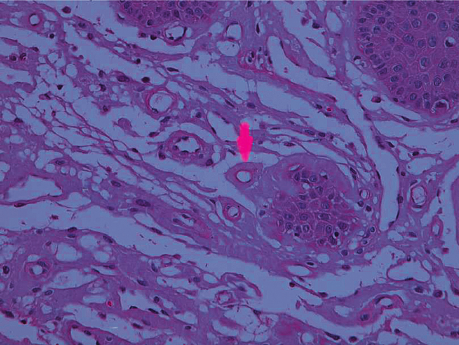

Dermoscopy And Clinicohistopathological Profile of Lichen Planopilaris Restricted To The Face: A Case Series Of Six Unusual Cases

This paper was presented by Drs Rohit Kothari, Sunmeet Sandhu, from the Air Force Hospital, Kanpur, Indiaon June 27th 2023